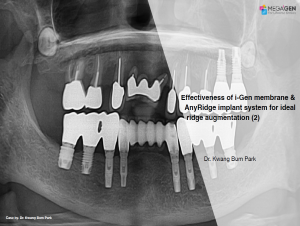

Effectiveness of i-Gen membrane & AnyRidge implant system for ideal ridge augmentation (2)

Dr. Kwang Bum Park,Aesthetic zone,Bone regeneration,Immediate loading,Maxillary Anterior,#17,#15,#13,#21,#23,#25,GBR,AnyRidge,i-Gen,Clinical case

English

2019-10-01

PDF

33.35 Mb

Clinical cases

202